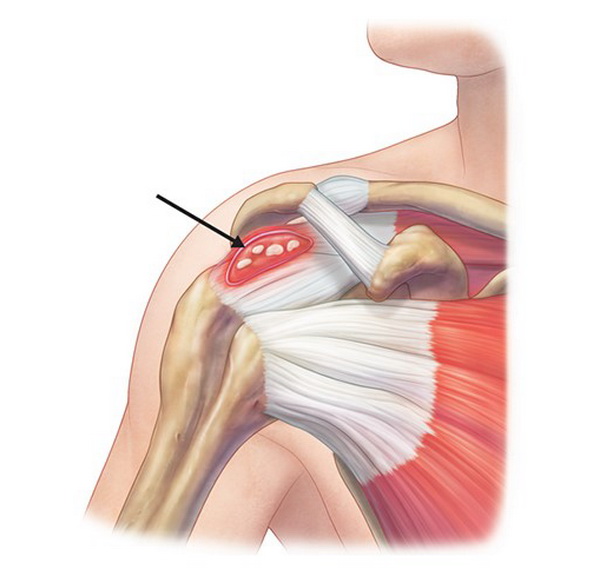

Фотографии поддельтовидной мышцы плечевого сустава